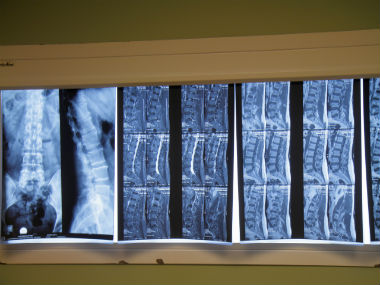

We’ve all heard horror stories about the guy in the gym who lifted incredible amounts of weight till one day he slipped a disc. Or about that one colleague who smoked incessantly and herniated a disc one fine day, just walking her dog. Slipped disc or disc herniation is an incredibly common and painful condition that affects the spine. [caption id=“attachment_7504341” align=“alignleft” width=“380”]  Representational image. Image source: Getty Images[/caption] On World Spine Day today (16 October), here’s everything you need to know about the spine and why spinal discs sometimes come out of alignment.